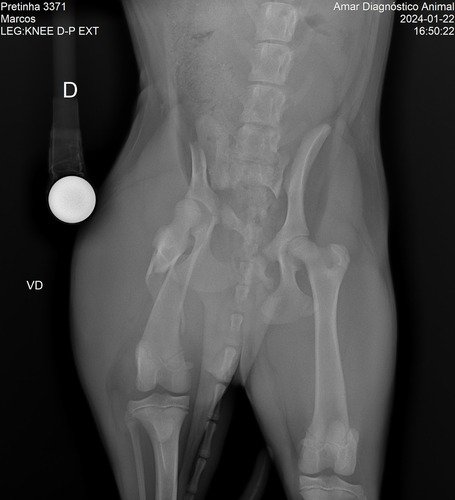

Meu nome é Flávia e moro aqui em Mogi Guaçu, interior de SP. No bairro onde eu moro infelizmente acontece muitos casos de abandono de animais, especialmente cachorros. Foi o caso dessa menininha linda da foto. Ela foi abandonada junto com sua mamãe e mais duas irmãzinhas. Infelizmente no último dia 21 de janeiro, a Belinha foi atropelada e o motorista fugiu sem prestar socorro. Depois de uma vaquinha comunitária e ajudas para as primeiras consultas e o Raio-X, foi constatada lesões na perninha direita, na bacia e baço, sendo então indicado um procedimento cirúrgico para que essa menininha amorosa possa continuar vivendo. Ainda não temos os custos finais para a cirurgia, mas certamente não sairá tão barato, pois além do procedimento também terá todo o processo do pós operatório. E é por isso que estamos abrindo essa Vakinha virtual para ajudar a custear a cirurgia e pós dela. Depois de recuperada, esperamos encontrar um lar lindo e feliz para ela, para sua irmãzinha e para sua mamãe. Nos ajude com qualquer valor. Caso consigamos algum excedente, vamos doar para ONGs que cuidam de animais aqui em nossa cidade. Que Deus os abençoe e guarde!!